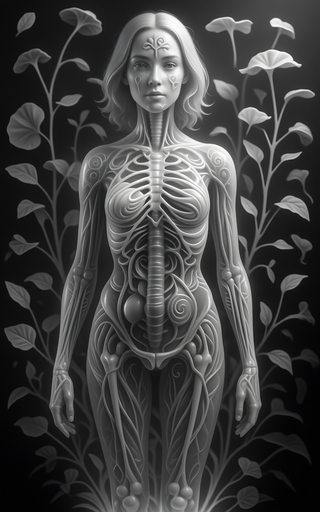

Creates ultra-detailed, multi-layer 3D anatomical visualizations from reference photos.Open

Creates ultra-detailed, multi-layer 3D anatomical visualizations from reference photos.Open

Transform photos into scientific anatomical illustrations.Open

Transform photos into scientific anatomical illustrations.Open